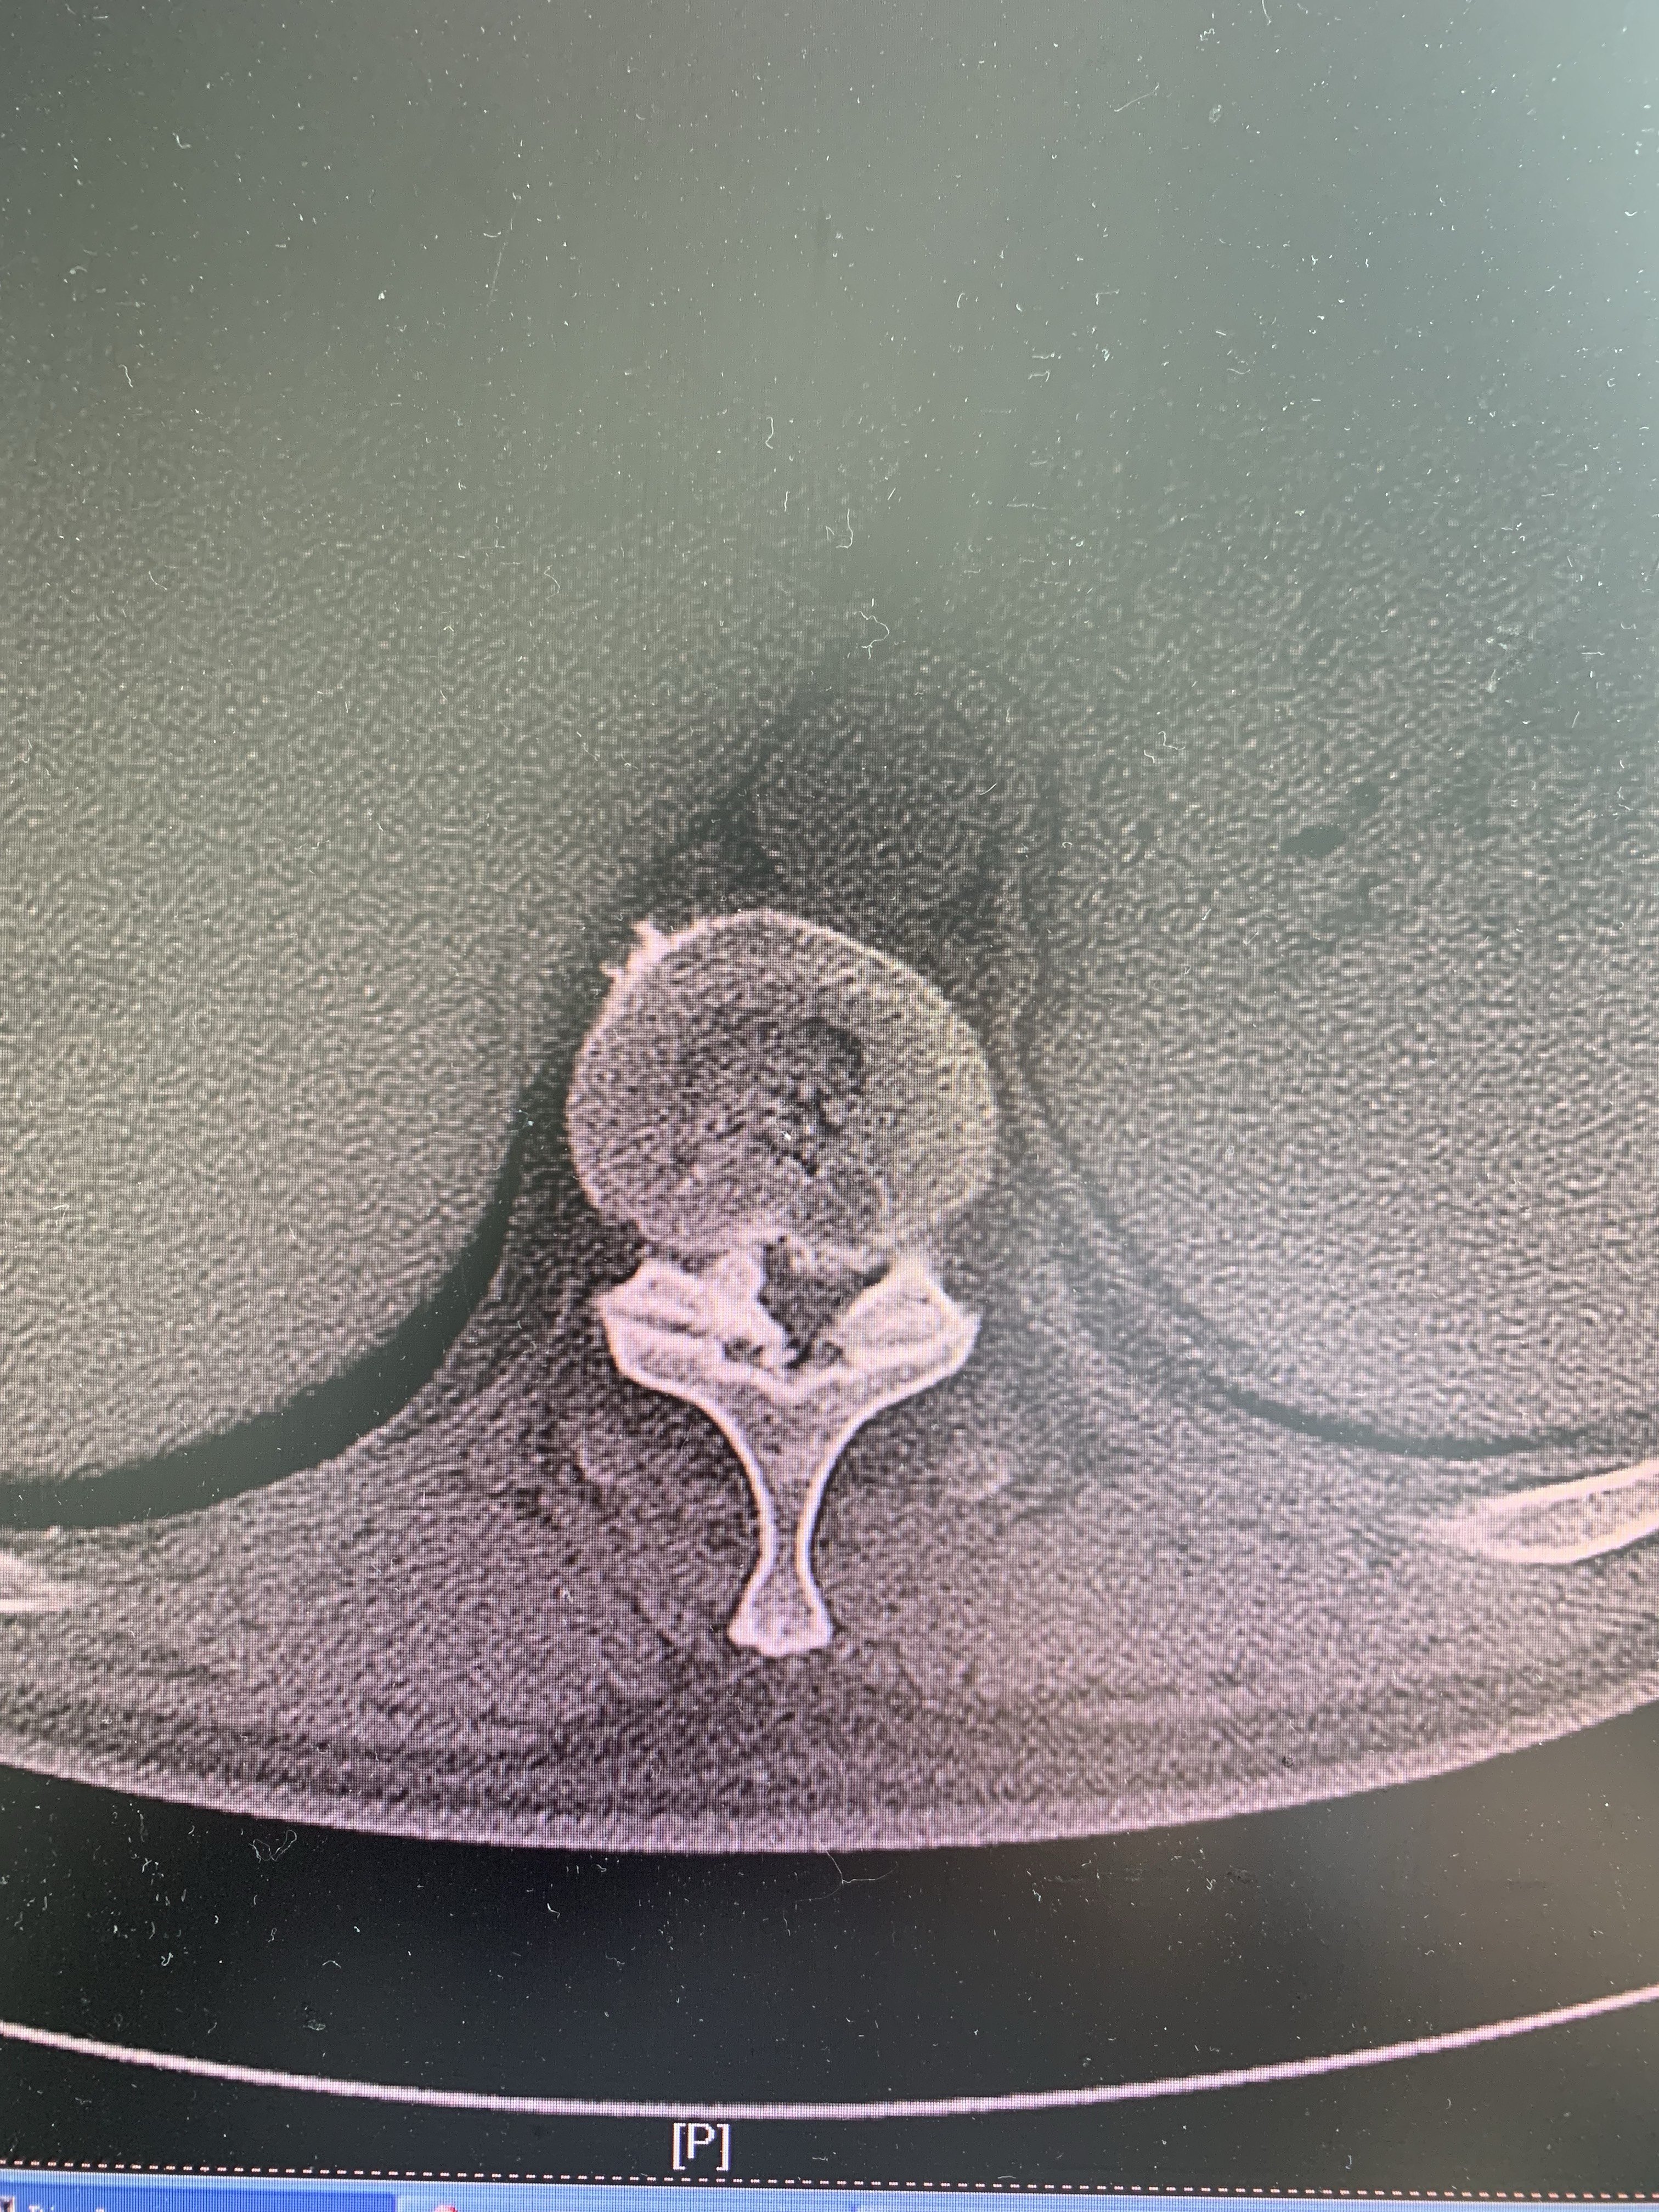

右侧黄韧带钙化,椎管严重狭窄

一侧黄韧带骨化另一侧椎间盘突出,脊髓被严重挤压变形,患者双下肢无力,不能正常行走。

节段平扫CT,巨大的钙化骨赘嵌入椎管内。

脊髓被压迫几乎成一条线。